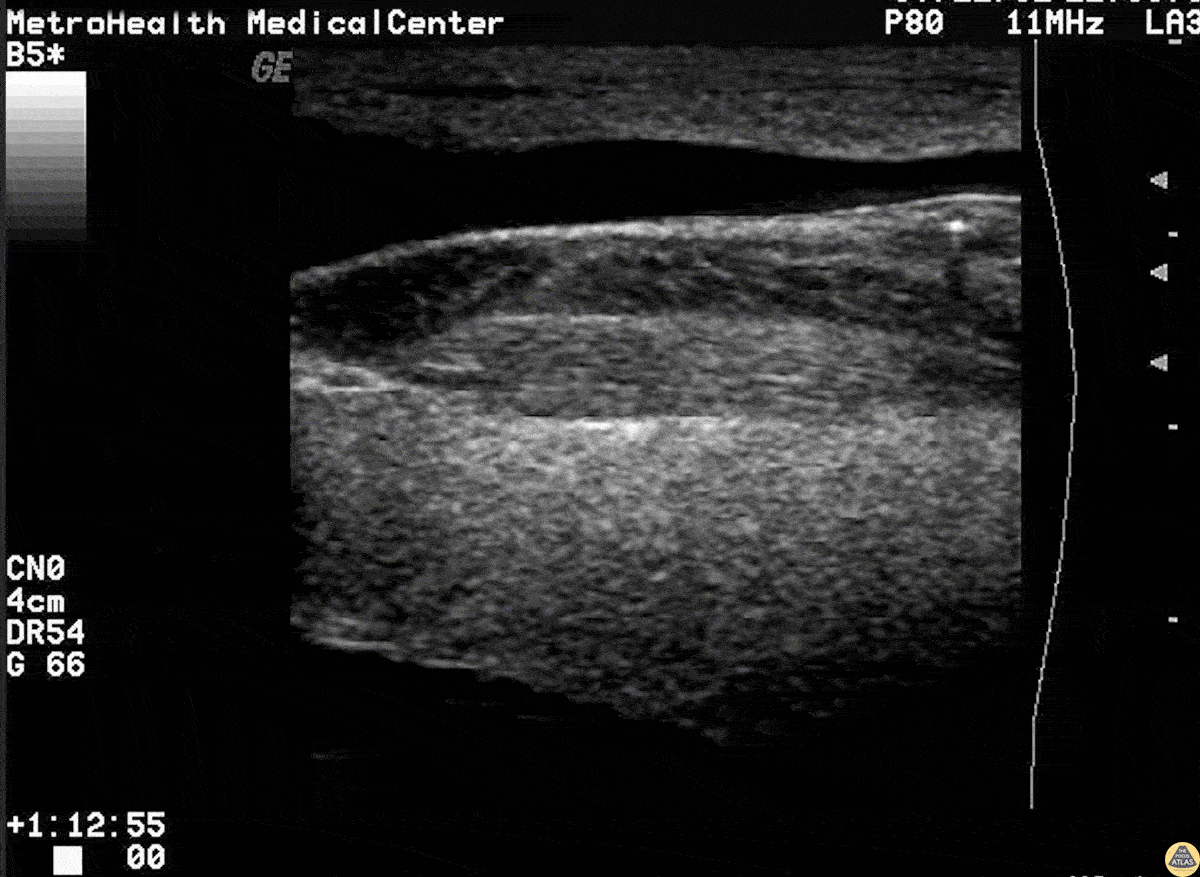

This is a short axis view of a needle that is broken off just posterior to the external jugular. Note the posterior acoustic shadowing. Image courtesy of Robert Jones DO, FACEP @RJonesSonoEM Director, Emergency Ultrasound; MetroHealth Medical Center; Professor, Case Western Reserve Medical School, Cleveland, OH View his original post here